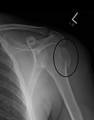

A fracture of the greater tubercle as seen on AP X ray

A fracture of the greater tubercle of the humerus

Fracture of the greater tubercle of the humerus

Fracture of the proximal humerus with involvement of the greater tubercle